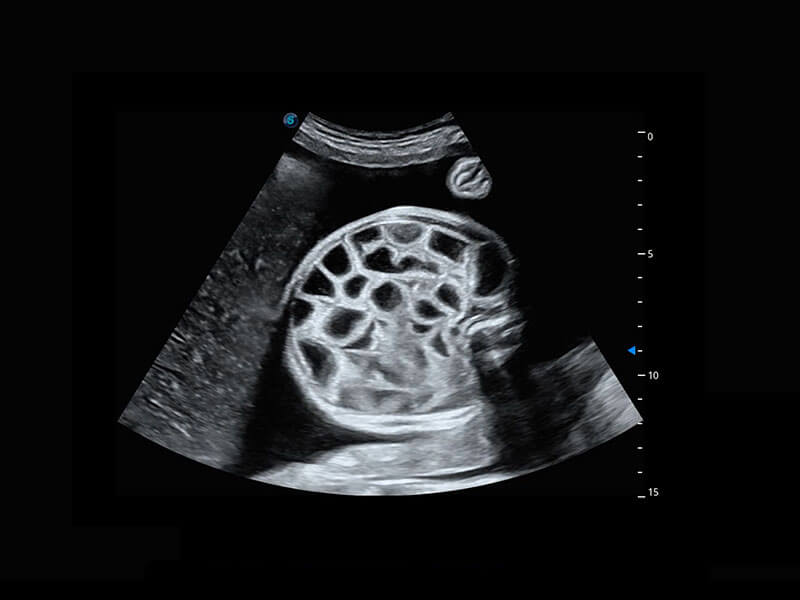

• 四腔切面

• 四腔心血流

• 右室双出口

• 胎心容积成像

P60搭载一系列胎儿心脏成像技术,实现精细的胎儿心脏评估。